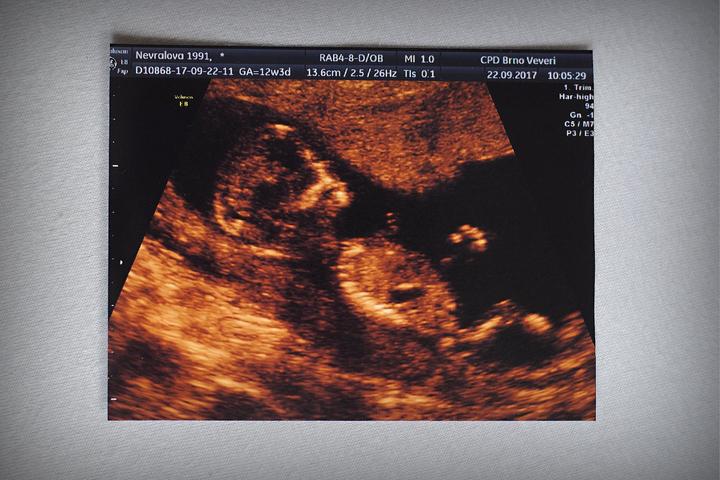

Problémy s otěhotněním a boj o početí potomka je velmi psychicky náročné životní období pro každý pár, který si tímto maratonem musí projít. Často řešíme, jak se cítí ženy. Jejich trápení, zoufalství, zběsile bezútěšně tikající biologické hodiny…. Ale co muži? Na ty se bohužel často zapomíná. Přitom je to pro ně také velmi stresující situace. Když opomeneme nutné vyšetření ejakulátu – spermiogram, které je v podstatě řízenou ejakulací do odběrového kelímku, tak je zde obrovský stres z možnosti selhání. To muži nesou velmi těžce. V případě, že je sperma nekvalitní – je to velká rána pro mužské ego.

O problému s početím mluvíme ve chvíli, kdy po roce nechráněného styku nedojde k otěhotnění. Poté by mělo následovat několik základních vyšetření a pak eventuálně návštěva IVF centra.